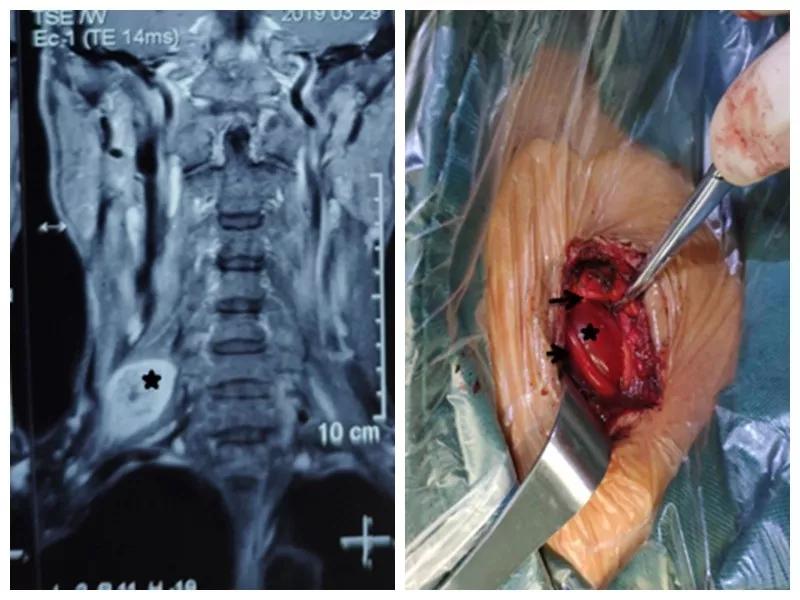

家住户县的王师傅一年前无意中发现右颈部长了一个“包”,当时并未在意,但是他发现这个“包”逐渐增大,并且伴有压痛,按压这个“包”时还可引起右胳膊疼痛,在当地医院就诊,未见好转,在我市某三甲医院检查及包块穿刺活检示右侧颈部神经鞘瘤,医生告诉他可以手术切除,但是风险很大。王师傅慕名来到六合彩生肖 骨一科就诊,严少荣主任接诊后立即安排住院治疗,并安排由西安市手外科常委王涛主任医师及主治医师张磊组成治疗小组。积极进行术前检查,发现右颈部肿瘤有3×3×3 cm大小活动性差的肿瘤。并有触电样感觉向肢体放射。经过制定缜密手术方案,严主任细心耐心告知患者手术的风险性,并安排术中神经电生理监测,提高手术安全性,由王涛主任医师、张磊主治医师和麻醉医师李楠及手术护士组成手术团队,在全麻下行右侧颈部神经鞘瘤切除术,术中发现此神经鞘膜瘤巨大,位于臂丛神经上干并包饶颈5.6神经,与周围组织黏连严重,由于该肿瘤起源于神经根纤维许旺氏细胞,遂着肿瘤不断生长,将神经干内正常神经纤维挤向肿瘤四周,包含在神经外膜内形成肿瘤的“包膜”呈鱼肉样。王涛主任医师在仔细保护神经的情况下采用“层层剥离挤出法”将肿瘤取除,避免了误将含正常神经纤维的“包膜”随肿瘤一起切除,造成神经干损伤及缺失,从而造成上肢功能的不可逆障碍的悲剧。术后经过主管护士解妍及全体医护人员的精心治疗护理,王师傅原有神经压迫症状消失,无任何感觉运动异常,术后再次病检符合神经鞘瘤。王师傅满意出院。

通过此例罕见臂丛神经上干神经鞘瘤病人治疗,标志着我科在高位臂丛神经干手术达到一个新高度。